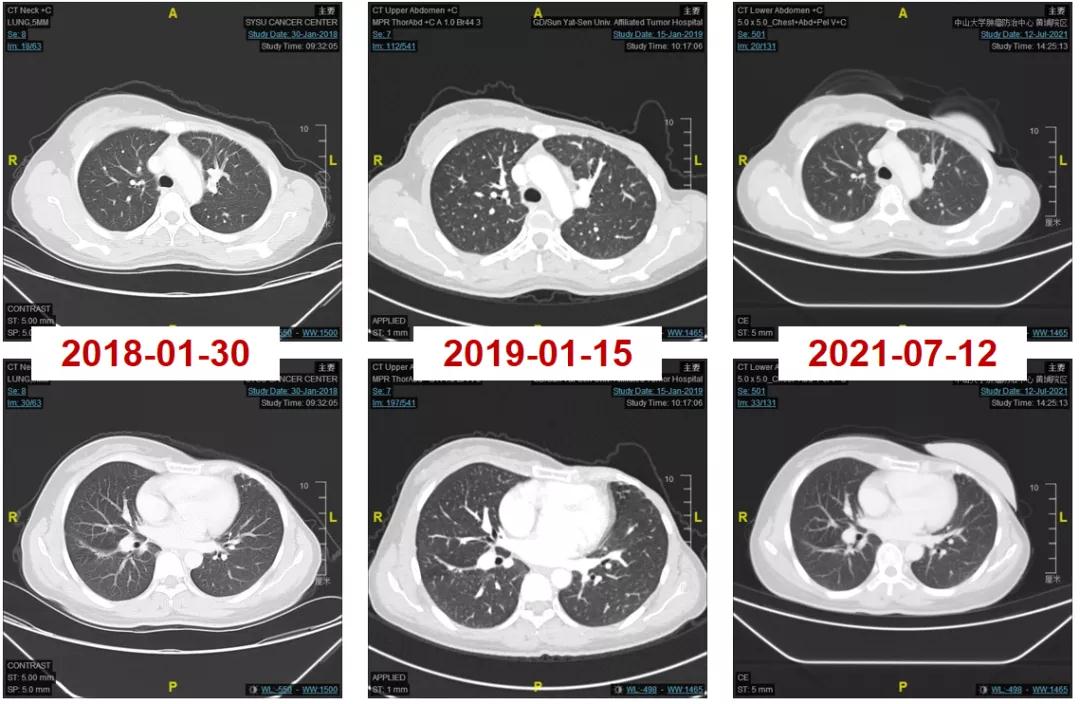

2016-06-01复查CT:右肺下叶上段团块状肿物(图1),考虑转移。

图1